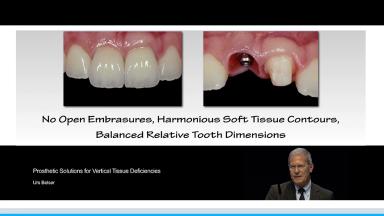

Prosthetic Solutions for Vertical Tissue Deficiencies

This lecture addresses the clinical challenges of addressing vertical tissue deficiencies in patients with esthetic demands. A literature review is presented that highlights publications that address treatment of patients with compromised esthetic situations due to these tissue deficiencies.

The speaker offers clinical recommendations to address single- and extended-tooth situations that require pink tissue replacement, with the goal of creating harmonious soft tissue contours and balanced relative tooth dimensions. Advantages and disadvantages to prosthetic tissue replacement are also covered in detail.